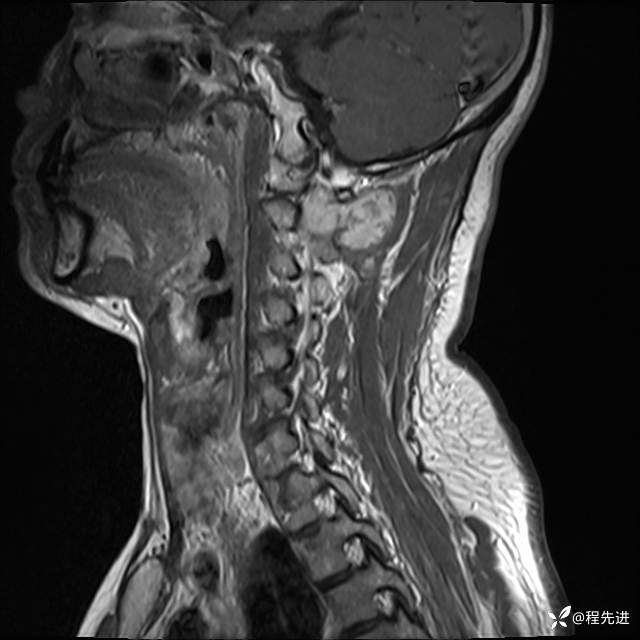

MRI平扫+增强:

T1增强: